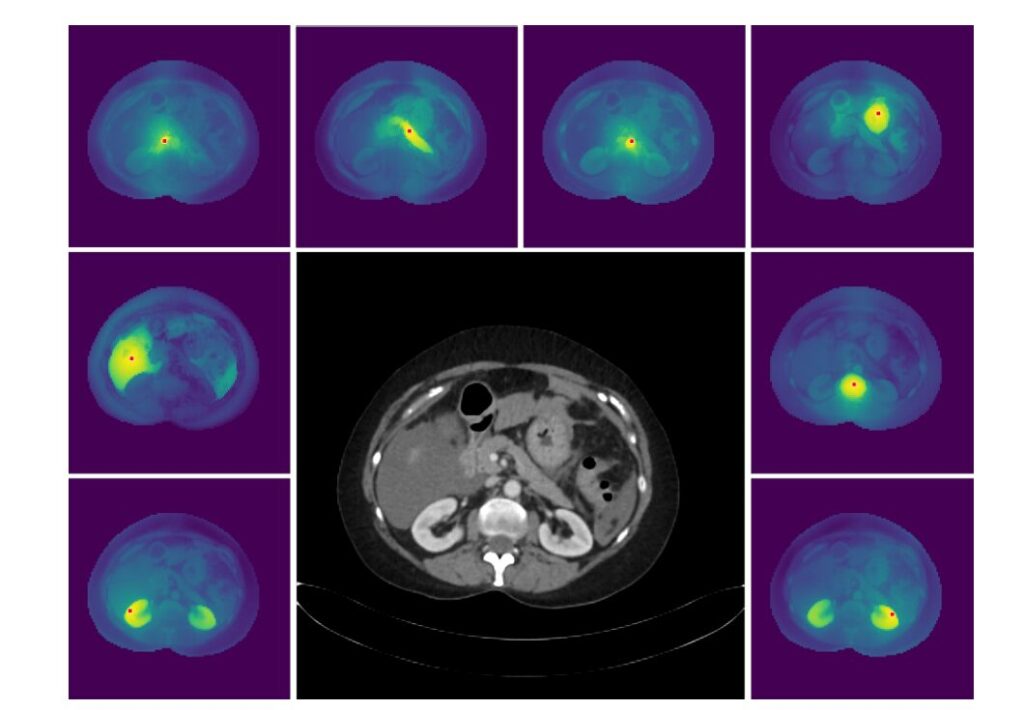

Image Description: Figure 3 – High-Resolution Dense Features of MedDINOv3.

- Alt Text: “Visualization of MedDINOv3’s cosine similarity map on a 2048×2048 CT scan. A red dot marks a reference patch, and the map shows its similarity to all other patches, demonstrating the model’s ability to capture fine-grained, high-resolution anatomical details.”